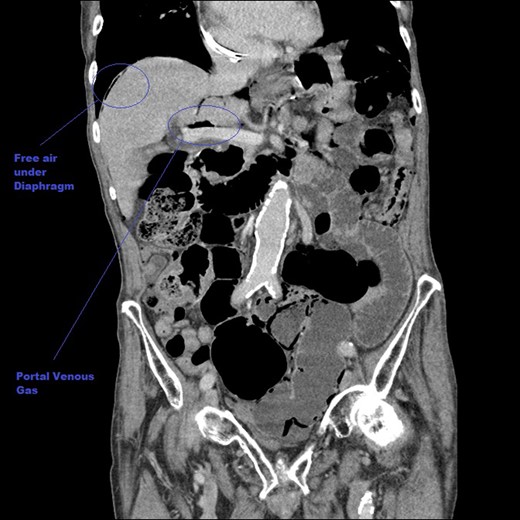

A coronal CT image of the abdomen taken at initial presentation, demonstrating free air under the diaphragm (pneumoperitoneum) and PVG, both marked on images.

Baseline bloods (including a lactate) were found to be normal. A CT scan demonstrated significant free intra-peritoneal air (Figs 1–3). Circumferential and linear intra-mural gas within the small bowel was seen consistent with PI. Small locules of air were seen in close proximity to the liver which was suggestive of PVG in the peripheral portal system. A faecal calprotectin level was also sent; this was later found to be negative.